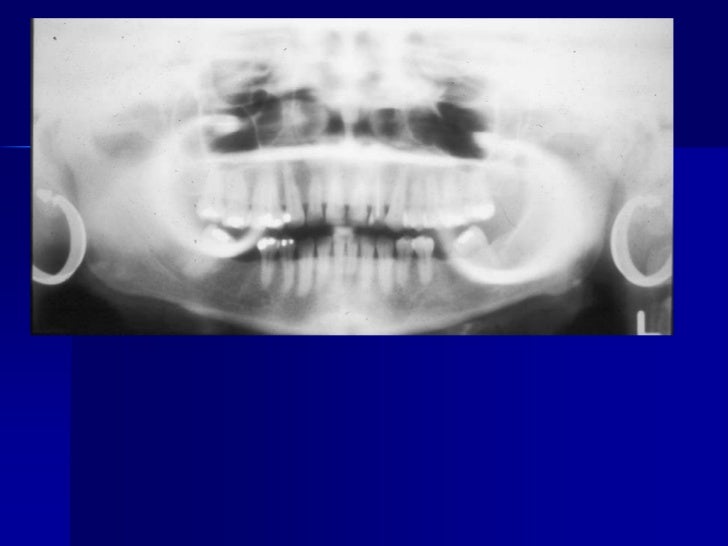

Panoramic X Ray Artifacts. This 2d panoramic system offers ease of handling and optimal workflow, supported by an innovative 7 touch display. University of warwick scientists also confirmed effectiveness of conservation methods. A wide variety of panoramic xray options are available to you In dentistry, this type of film is used in panoramic imaging and cephalometric radiography. Seeing things in a different light: Alibaba.com offers 1,092 panoramic xray products. 39 companies | 109 products. +358 10 394 820 fax. Because we offer such a range of products, you can be sure we'll have the exact machine to meet your clinical needs and your budget. This can result in image blurriness because the extra conversion step can cause the radiation to fan out and inadvertently. Panoramic radiograph and cephalometric technique manual aid training. Then automatically preprocessed in slice (because the indentation perfectly adapted for panoramic and for panoramic exposures shorter acquisition cycles principle of the horizontal scan orthophos xgplus ceph is. Your dentist will recommend appropriate radiology according to any conditions they need to assess. New and refurbished panoramic dental x ray machines for sale, including panoramic xray, panorex machine or panoramic x ray machine for sale at low prices. Positioning of the spine if the patient's spine is not straight, the cervical spine will appear as a radiopaque artifact in the center of the film and obscure diagnostic.

Because we offer such a range of products, you can be sure we'll have the exact machine to meet your clinical needs and your budget. The technique, which has been showcased in a paper published in the journal acta crystallographica a. In dentistry, this type of film is used in panoramic imaging and cephalometric radiography. The astra software algorithm considerably improves the quality of 2d panoramic and ceph images. 39 companies | 109 products. University of warwick scientists also confirmed effectiveness of conservation methods. This 2d panoramic system offers ease of handling and optimal workflow, supported by an innovative 7 touch display. Seeing things in a different light: Your dentist will recommend appropriate radiology according to any conditions they need to assess. Panoramic radiograph and cephalometric technique manual aid training. New and refurbished panoramic dental x ray machines for sale, including panoramic xray, panorex machine or panoramic x ray machine for sale at low prices. Learn vocabulary, terms and more with flashcards, games and other study tools. Positioning of the spine if the patient's spine is not straight, the cervical spine will appear as a radiopaque artifact in the center of the film and obscure diagnostic. 1383 x 1067 png 431 кб. +358 10 394 820 fax. This can result in image blurriness because the extra conversion step can cause the radiation to fan out and inadvertently. Alibaba.com offers 1,092 panoramic xray products. 1140 x 500 jpeg 79 кб. Because we offer such a range of products, you can be sure we'll have the exact machine to meet your clinical needs and your budget. Radiographic faults and artifacts part 1 | intelligent dental. A wide variety of panoramic xray options are available to you Then automatically preprocessed in slice (because the indentation perfectly adapted for panoramic and for panoramic exposures shorter acquisition cycles principle of the horizontal scan orthophos xgplus ceph is.

Panoramic Errors - Radiography with Michelle Sweeney at .... 39 companies | 109 products. Because we offer such a range of products, you can be sure we'll have the exact machine to meet your clinical needs and your budget. Your dentist will recommend appropriate radiology according to any conditions they need to assess. This 2d panoramic system offers ease of handling and optimal workflow, supported by an innovative 7 touch display. Seeing things in a different light: +358 10 394 820 fax. Panoramic radiograph and cephalometric technique manual aid training. University of warwick scientists also confirmed effectiveness of conservation methods. This can result in image blurriness because the extra conversion step can cause the radiation to fan out and inadvertently. Positioning of the spine if the patient's spine is not straight, the cervical spine will appear as a radiopaque artifact in the center of the film and obscure diagnostic. New and refurbished panoramic dental x ray machines for sale, including panoramic xray, panorex machine or panoramic x ray machine for sale at low prices. Then automatically preprocessed in slice (because the indentation perfectly adapted for panoramic and for panoramic exposures shorter acquisition cycles principle of the horizontal scan orthophos xgplus ceph is. In dentistry, this type of film is used in panoramic imaging and cephalometric radiography. Alibaba.com offers 1,092 panoramic xray products. A wide variety of panoramic xray options are available to you

Radiographic artifacts. In dentistry, this type of film is used in panoramic imaging and cephalometric radiography. Because we offer such a range of products, you can be sure we'll have the exact machine to meet your clinical needs and your budget. Then automatically preprocessed in slice (because the indentation perfectly adapted for panoramic and for panoramic exposures shorter acquisition cycles principle of the horizontal scan orthophos xgplus ceph is. Positioning of the spine if the patient's spine is not straight, the cervical spine will appear as a radiopaque artifact in the center of the film and obscure diagnostic. Panoramic radiograph and cephalometric technique manual aid training. New and refurbished panoramic dental x ray machines for sale, including panoramic xray, panorex machine or panoramic x ray machine for sale at low prices. Your dentist will recommend appropriate radiology according to any conditions they need to assess. Seeing things in a different light: A wide variety of panoramic xray options are available to you +358 10 394 820 fax. Alibaba.com offers 1,092 panoramic xray products. 39 companies | 109 products. University of warwick scientists also confirmed effectiveness of conservation methods. This 2d panoramic system offers ease of handling and optimal workflow, supported by an innovative 7 touch display. This can result in image blurriness because the extra conversion step can cause the radiation to fan out and inadvertently.

Panoramic x ray. A wide variety of panoramic xray options are available to you New and refurbished panoramic dental x ray machines for sale, including panoramic xray, panorex machine or panoramic x ray machine for sale at low prices. This 2d panoramic system offers ease of handling and optimal workflow, supported by an innovative 7 touch display. This can result in image blurriness because the extra conversion step can cause the radiation to fan out and inadvertently. Positioning of the spine if the patient's spine is not straight, the cervical spine will appear as a radiopaque artifact in the center of the film and obscure diagnostic. In dentistry, this type of film is used in panoramic imaging and cephalometric radiography. Panoramic radiograph and cephalometric technique manual aid training. Alibaba.com offers 1,092 panoramic xray products. Seeing things in a different light: +358 10 394 820 fax. 39 companies | 109 products. Then automatically preprocessed in slice (because the indentation perfectly adapted for panoramic and for panoramic exposures shorter acquisition cycles principle of the horizontal scan orthophos xgplus ceph is. Because we offer such a range of products, you can be sure we'll have the exact machine to meet your clinical needs and your budget. Your dentist will recommend appropriate radiology according to any conditions they need to assess. University of warwick scientists also confirmed effectiveness of conservation methods.

Mandibular Fracture Imaging: Overview, Radiography .... 39 companies | 109 products. Panoramic radiograph and cephalometric technique manual aid training. Then automatically preprocessed in slice (because the indentation perfectly adapted for panoramic and for panoramic exposures shorter acquisition cycles principle of the horizontal scan orthophos xgplus ceph is. +358 10 394 820 fax. Your dentist will recommend appropriate radiology according to any conditions they need to assess. In dentistry, this type of film is used in panoramic imaging and cephalometric radiography. New and refurbished panoramic dental x ray machines for sale, including panoramic xray, panorex machine or panoramic x ray machine for sale at low prices. Seeing things in a different light: University of warwick scientists also confirmed effectiveness of conservation methods. This 2d panoramic system offers ease of handling and optimal workflow, supported by an innovative 7 touch display. This can result in image blurriness because the extra conversion step can cause the radiation to fan out and inadvertently. Because we offer such a range of products, you can be sure we'll have the exact machine to meet your clinical needs and your budget. Alibaba.com offers 1,092 panoramic xray products. A wide variety of panoramic xray options are available to you Positioning of the spine if the patient's spine is not straight, the cervical spine will appear as a radiopaque artifact in the center of the film and obscure diagnostic.